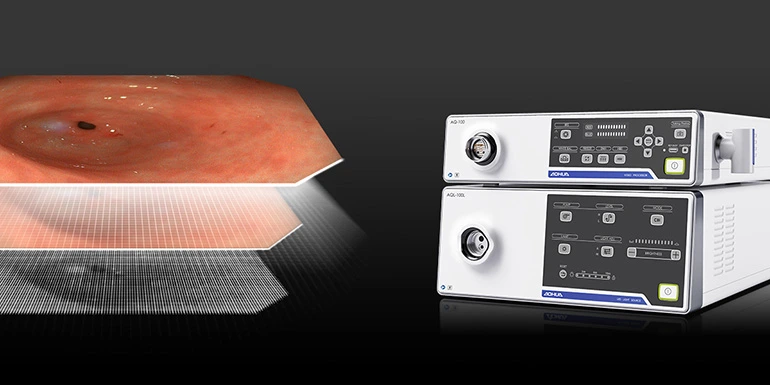

Видеоэндоскопическая система на базе Aohua AQ-110

Видеоэндоскопическая система Aohua AQ-110 Full HD - это отличная визуализация и потрясающий функционал. Данная видеоэндоскопическая система создана на основе видеопроцессора Aohua AQ-110.

Видеоэндоскопическая система Aohua AQ-110 предлагает вам широкий выбор эндоскопов и функций, а также улучшенное разрешение формата Full HD. Совместима с диагностическими и терапевтическими эндоскопами для ЖКТ, видеобронхоскопами и видеоларингооскопами.

Изображение в формате Full HD

Матрица Full HD CMOS используется для получения высококачественных изображений. Позволяет добиться четкого и резкого контраста по краям между поверхностями разных тканей, обеспечивая превосходные изображения и отличную детализацию.